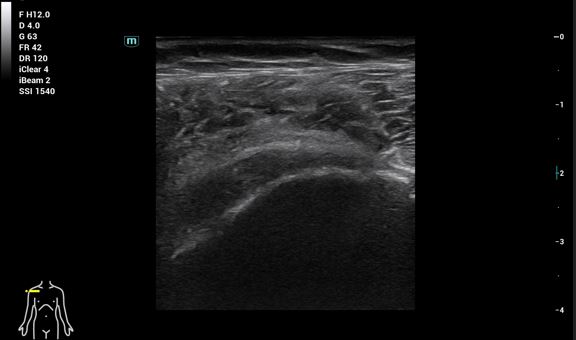

Se realiza ecografía hombro derecho para ayudarnos con el diagnóstico diferencial: tumores sólidos, quistes o gangliones de contenido líquido.

Ecografía de hombro derecho: Lesión multilobulada anecoica, sin claro refuerzo posterior, bien delimitada con paredes gruesas. Doppler negativo.

RMN: Cambios hipertróficos en la articulación acromio-clavicular con líquido e imagen de ganglión de unos 5 cm. Desgarro del manguito de los rotadores con desgarro completo del tendón supraespinoso. Desgarro del tendón infraespinoso, del tendón subescapular, del redondo menor y del tendón de la cabeza larga del bíceps braquial. Líquido en la bolsa subacromiosubdeltoidea y subcoracoidea.